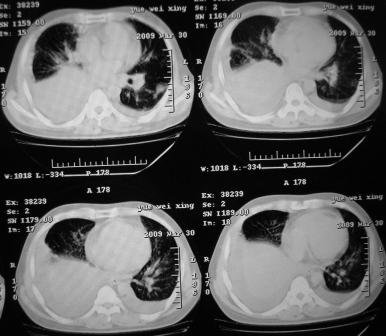

xx 男 43岁

右肺下叶支气管中断闭塞,右下肺见不规块影,并胸腔积液,考虑肺中央型肺癌继发下叶不张,\\双侧胸腔积液,心包积液。

考虑右中央型肺癌并下叶不张,双侧胸腔积液,心包积液

右侧中央型肺癌伴右肺下叶不张,双肺及纵隔淋巴转移,双侧胸腔积液,心包积液。

1)考虑右侧中央型肺癌伴右肺下叶不张,双肺及纵隔淋巴转移。2)双侧胸腔积液,以右侧为甚。3)心包积液。

考虑右侧中央型肺癌伴右肺下叶不张,双肺及纵隔淋巴转移,双侧胸腔积液。不除外结核。

考虑右肺下叶中心性肺癌并纵隔淋巴结、双肺转移伴右肺下叶阻塞性肺不张;双侧胸水,右侧为著;心包积液